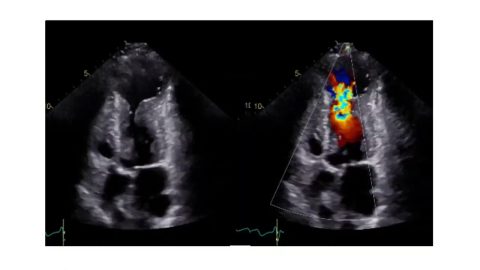

Thick Cardiac Wall

This video from ASE’s Microlesson Series on Hypertrophic Cardiomyopathy (HCM) answers the question, “In what disease states is the cardiac wall thickened?”